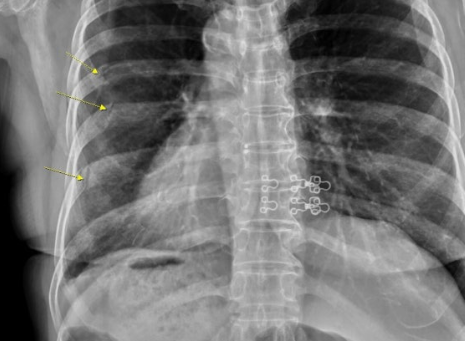

이 사고로 A씨는 좌측 늑골(갈비뼈) 골절과 우측 정강이 열상 등의 부상을 입었으며, 추석 연휴 기간 통원치료를 받은 뒤 지난달 20일 업무에 복귀한 것으로 알려졌다.